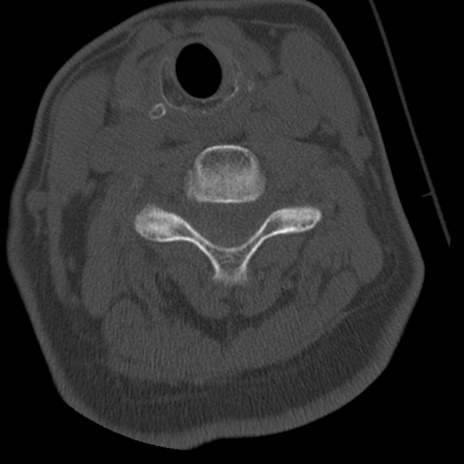

症例50 頚椎CT(横断像)

頚椎CT